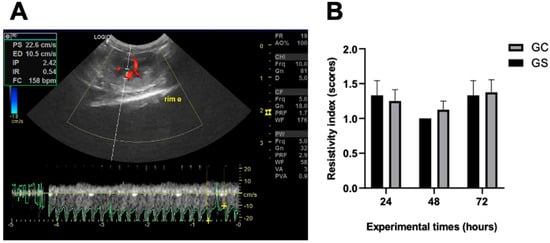

Doppler analysis revealed intact renal vasculature (Figure 4A), allowing for visualization and measurement in all animals regardless of the experimental time points. Regarding the renal resistive index and the pattern of renal blood flow (Figure 4B and Supplementary Material File S1), no significant differences (p > 0.05) were found between the groups.

Figure 4. Renal resistivity index. (A) Doppler ultrasonographic parameter revealing intact renal vasculature and resistivity index of the left kidney of an animal treated with cyclophosphamide (GC). (B) Graphical representation of Doppler ultrasonographic parameter regarding renal resistive index (score 1: low, score 2: intermediate, and score 3: high). PS: systolic speed; ED: diastolic velocity; PI: pulsatility index; IR: resistivity index; HR: heart rate. There were no statistical differences between the groups in the respective experimental moments.